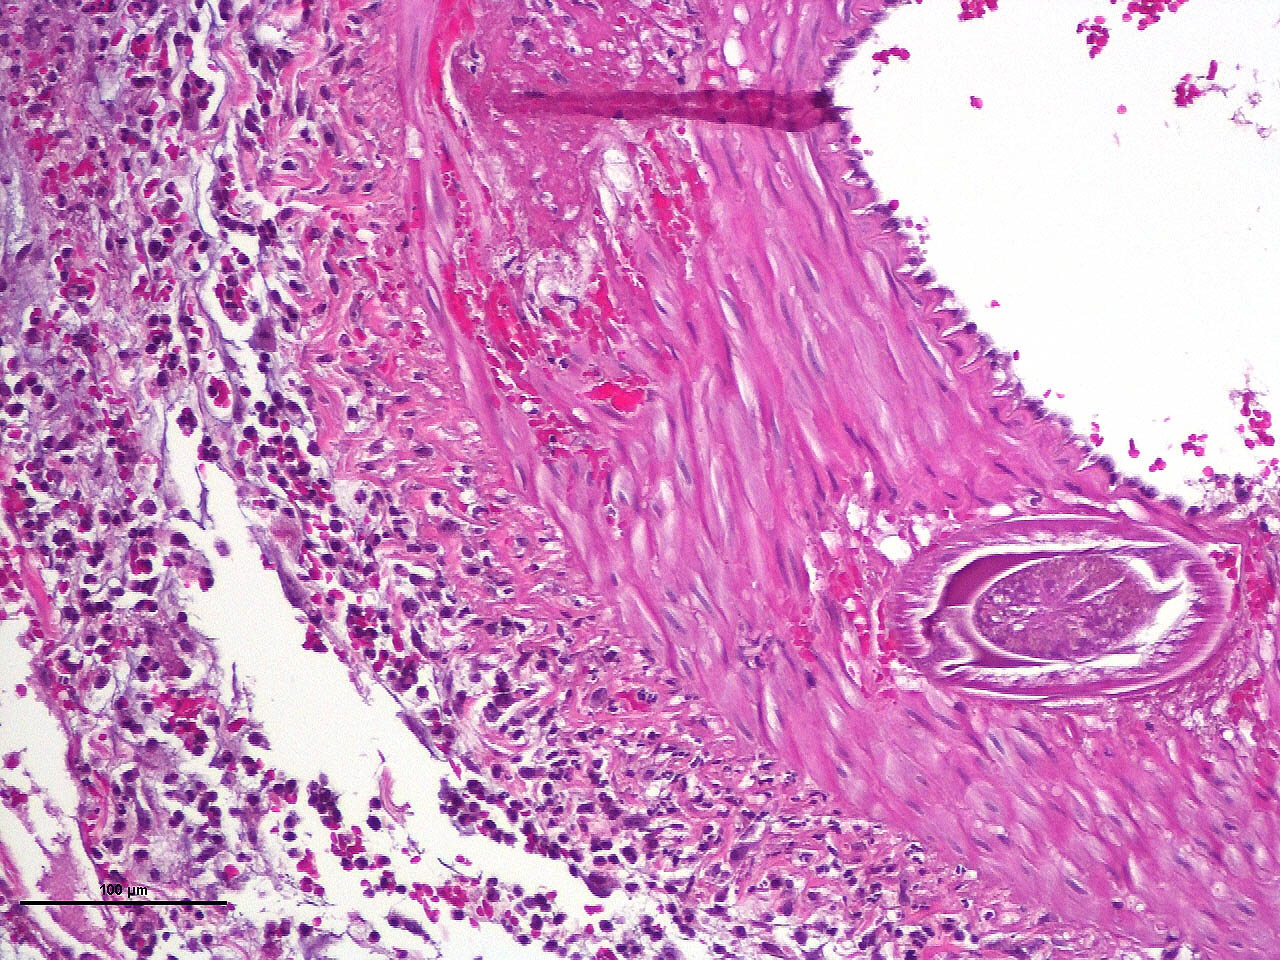

Within the media of medium to small sized arteries there were sections (not present in all slides due to the small size of the parasite – but see photomicrographs) of a nematode larva, approximately 100-200 µm in diameter with lateral allae and central digestive tract. These features are consistent with a spirurid of which Spirocerca is the most likely in our region. Foci of necrosis with hemorrhage were observed in the media of some arteries, where no larvae were identified.

Acute transmural necrotizing eosinophilic enteritis and eosinophilic peritonitis with arterial mesenteric thrombi and rare intralesional nematode larvae (spirurid)Contributor's Comment:

Third stage larvae of Spirocerca are ingested with beetles and penetrate the gastric mucosa. They move along arteries to the aorta and migrate in its wall to the thoracic region where they are found several weeks after ingestion. They incite granulomatous inflammation in the aorta and stay there for 2-4 months. Later, the larvae migrate to the esophagus where they mature in the submucosa and perforate the epithelium.2,7

Aortic lesions associated with Spirocerca include intimal and medial hemorrhage and necrosis with eosinophilic inflammation, thrombus formation and rarely rupture of the aortic wall.1,2,7

- Mesentery: Arteritis and periarteritis, necrotizing and eosinophilic, chronic, multifocal, severe, with arterial thrombi and rare larval spirurids.

The JPC’s own MAJ Katie Scott moderated Conference 6 and took participants on a journey of cases from around the world; each one was from somewhere outside of the continental U.S., highlighting the truly global nature of the WSC and the importance of international contributions to pathology education. This first case provided an excellent opportunity to review of the pathogenesis and life cycle of Spirocerca lupi, both of which are well-covered in the contributor’s comment. Additionally, the lesions of spirocercosis that are considered pathognomonic in the dog were covered and include aortic scarring with aneurysms, thoracic spondylitis, and caudal esophageal nodules. Special attention was paid to the chronic arterial thrombi present in numerous arteries in this case, which are a classic part of the pathogenesis of this parasite due to its arterial migratory routes and chronic intimal irritation. Participants were also reminded of the importance of specifying what type of vessels (arteries, arterioles, veins, lymphatics, etc.) are affected when giving a description, as this can provide important clues towards pathogenesis of some diseases that may preferentially affect a specific vessel type.Spirocerca lupi is one of a handful of helminths that are classified as Group I carcinogens by the International Agency for Research on Cancer (IARC) due to the well-documented malignant transformation of S. lupi esophageal nodules into esophageal fibrosarcomas or osteosarcomas in up to 25% of infected dogs.6 Less commonly, chondrosarcomas or undifferentiated pleomorphic sarcomas can also be seen.6 Metastasis to multiple locations throughout the body, including the lungs, kidneys, stomach, spleen, heart, and tongue, occurs frequently.6,7 Significantly higher levels of interleukin-8 (IL-8) have been documented in dogs with malignant esophageal nodules.4 IL-8 is released by activated fibroblasts in pre-neoplastic nodules and is chemotactic for neutrophils. IL-8 is also involved in the tumor progression of human herpesvirus-4 (Epstein–Barr virus)-induced carcinomas.4